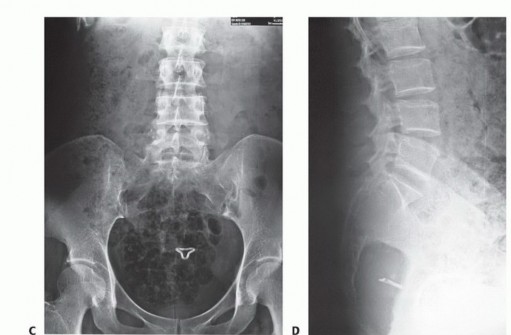

التصوير بالأشعة السينية العادية

قد تكون صور الأشعة السينية العادية غير واضحة في المراحل المبكرة من المرض. ومع ذلك، يمكن أن تساعد في تشخيص بعض الأورام، مثل الورم الحبلي الذي غالبًا ما يقع في الجزء السفلي من العجز، أو الأورام الكبيرة والمحللة تمامًا مثل ورم الخلايا العملاقة أو الكيس العظمي المتمدد في الجزء العلوي من العجز. تُعد الأشعة السينية ضرورية لإعطاء نظرة عامة ومتابعة ما بعد الجراحة.

التصوير المقطعي المحوسب والرنين المغناطيسي

- التصوير المقطعي المحوسب (CT): يُعد بتقنية التباين الوريدي الأسلوب الأمثل لتقييم مدى انتشار الورم في العظم وتدميره، والتكلسات المحتملة، والموقع التشريحي، والإمداد الدموي، وعلاقة الورم بالأعضاء الحشوية. يساعد في التفريق بين الأورام الحميدة والخبيثة.

- التصوير بالرنين المغناطيسي (MRI): بتقنية التباين، يُعد حاسمًا لتصوير الأنسجة الرخوة ومدى انتشار الورم فيها، وعلاقته بالأنسجة المحيطة (مثل الأوعية الدموية والأعصاب والعضلات والأعضاء الحشوية). يُعتبر الأسلوب الأمثل لتصوير الأنسجة الرخوة نظرًا لقدرته الفائقة على التمييز مقارنةً بالتصوير المقطعي.